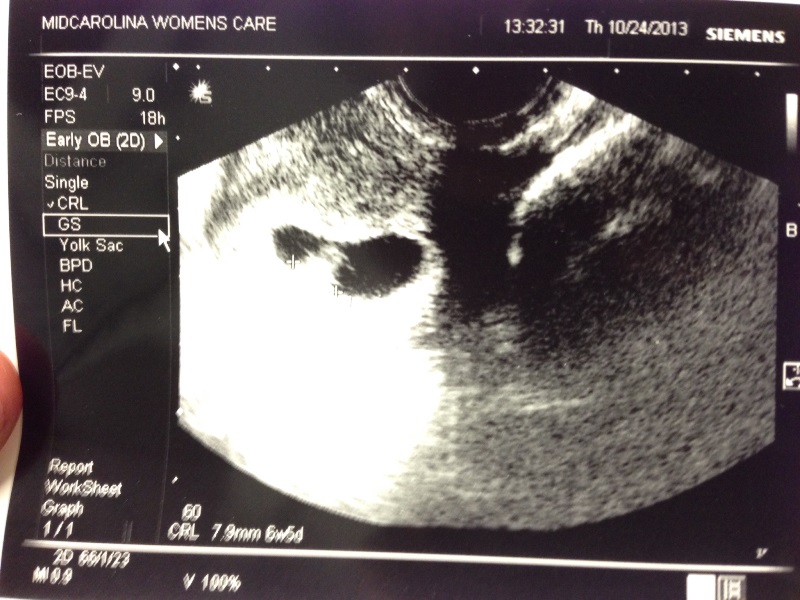

- We had our first ultrasound to date the pregnancy on October 24. Since I had so little symptoms, I was convinced that there was nothing actually in there. Thankfully, I was wrong.

Baby G’s first picture. Sonogram establishing my due date on Thursday, October 24, 2013. We celebrated by going out to buy our dining room table, lol.